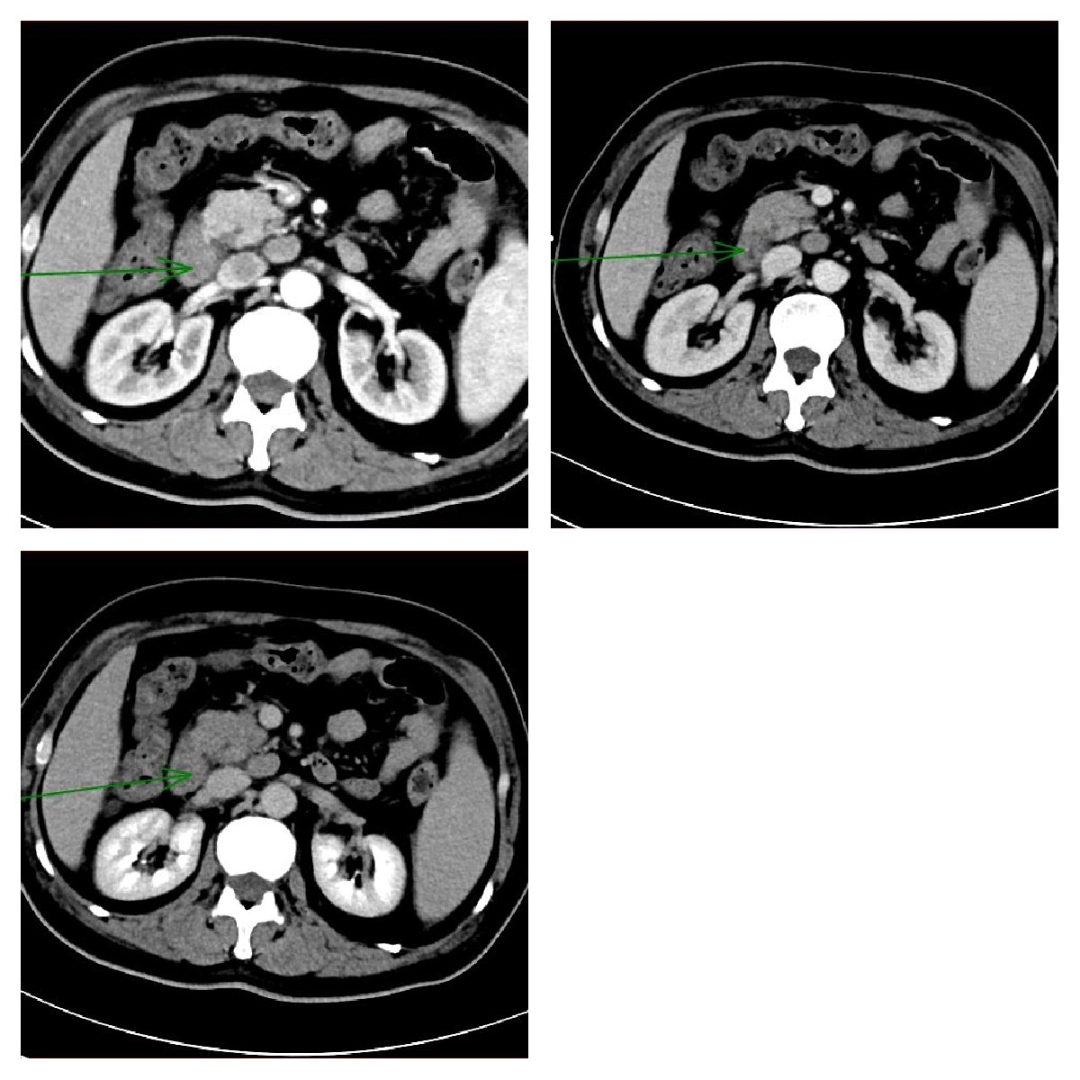

胰腺癌:胰腺是富血供器官、胰腺癌是乏血供肿瘤,因此表现为低信号肿物。